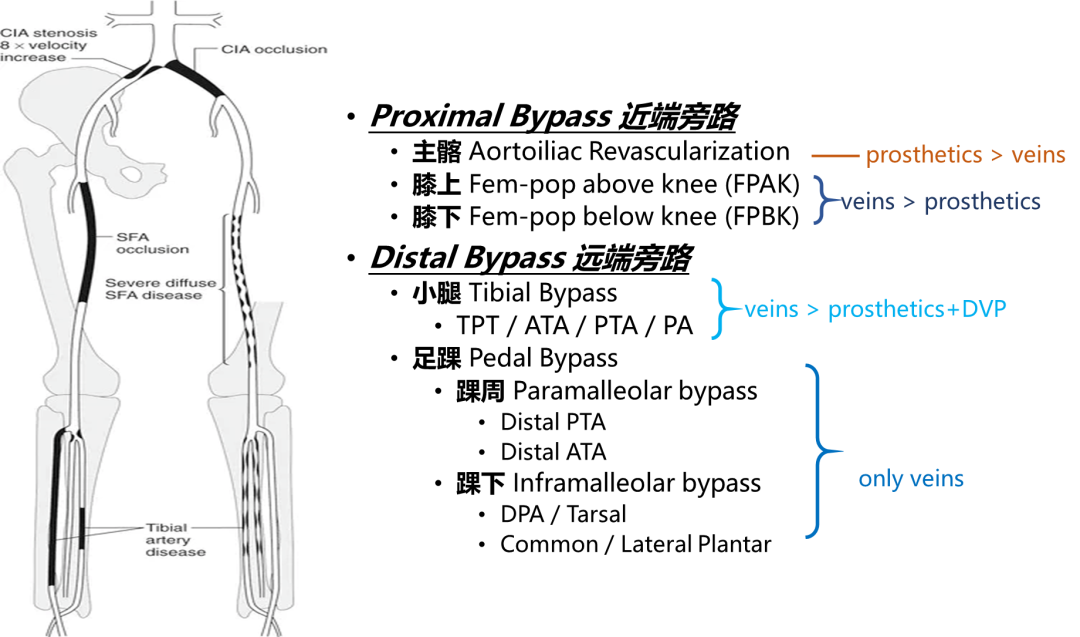

自体静脉仍是腹股沟以下旁路的金标准

所有腹股沟以下血管旁路手术,首选健康自体静脉

为什么需要更远端的旁路?

膝上股腘旁路(FPAK)可能即将被EVT所替代,故而旁路手术亟需面对更具挑战的远端病例

可以提供愈合伤口的充沛血流

The more distal, the more powerful